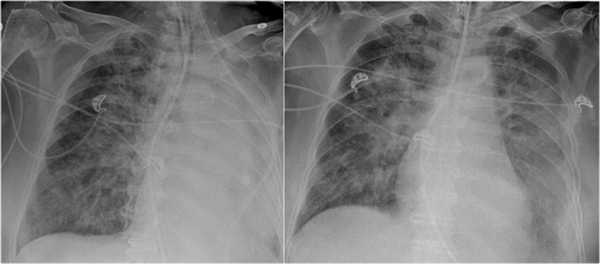

Мы видим его рентгенограммы за 2010-й год. Корень правого легкого расширен, уплотнен. Мы видим (неразборчиво термин, 15:29) изменения в переднем сегменте: уплотнение легочной ткани.

Как раз на фоне ухудшения состояния, повышения температуры было проведено рентгенологическое обследование. В данном случае мы видим, что у корня легкого появилась нечеткость контуров, увеличение воспалительных изменений верхней доли правого легкого.

Посмотрите в динамике эти два снимка за 2010-й и 2011-й год. Здесь, конечно, четко видна на последнем снимке отрицательная динамика.